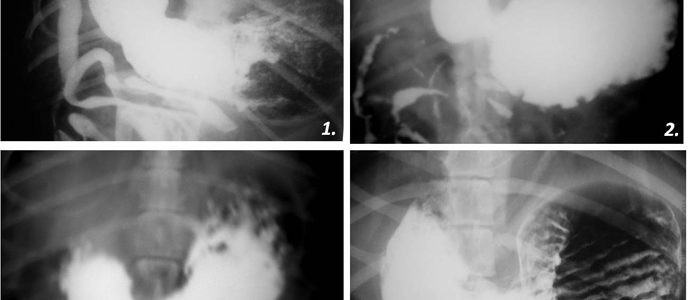

Современные технологии в медицине: рентгенодиагностика заболеваний желудка